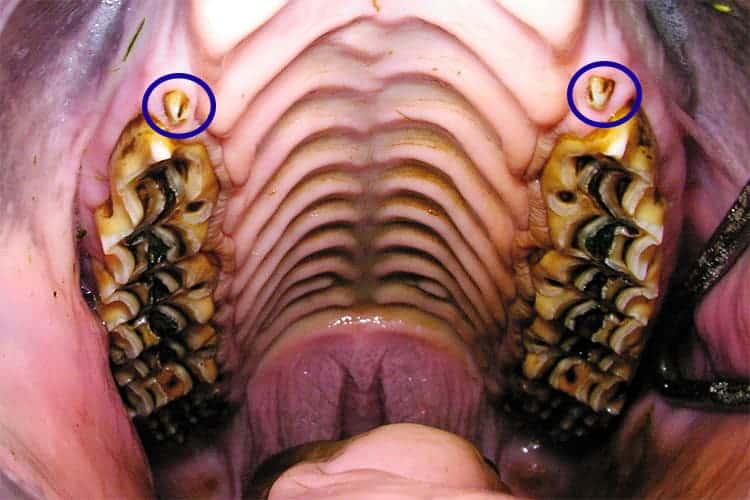

Equine Wolf Teeth

While these teeth usually don’t pose a health risk to the horse, they are often removed in performance horses.

While these teeth usually don’t pose a health risk to the horse, they are often removed in performance horses.